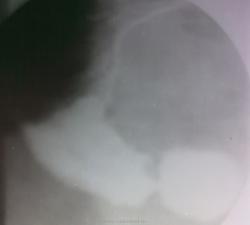

Грыжи пищеводного отверстия диафрагмы

Грыжи пищеводного отверстия диафрагмы часты. Тем более, что на цифровых флюорограммах ОГК хорошо видны и без контрастирования. Но такое у меня впервые...

Игорь Иванович, мне кажется, что осложнение данной грыжи есть неполный заворот желудка вокруг горизонтальной оси, картинка очень специфична.

Может быть. Меня больше юольше интересовало дно желудка, что бы без дефектов..

Снимки стоя, как я понимаю, явно на дефекты не смахивает. но при такой деформации и перегибе надо быть начеку....може еще пусть эндоскописты заглянут...для пущей уверенности...

Короче, это наша коллега, возрастом под 90. Говорит, что и раньше ей говорили о грыже, только не известно, каких объемов. В общем, Виктор Григорьевич, побеседовали с тобой через "New Vasuki"